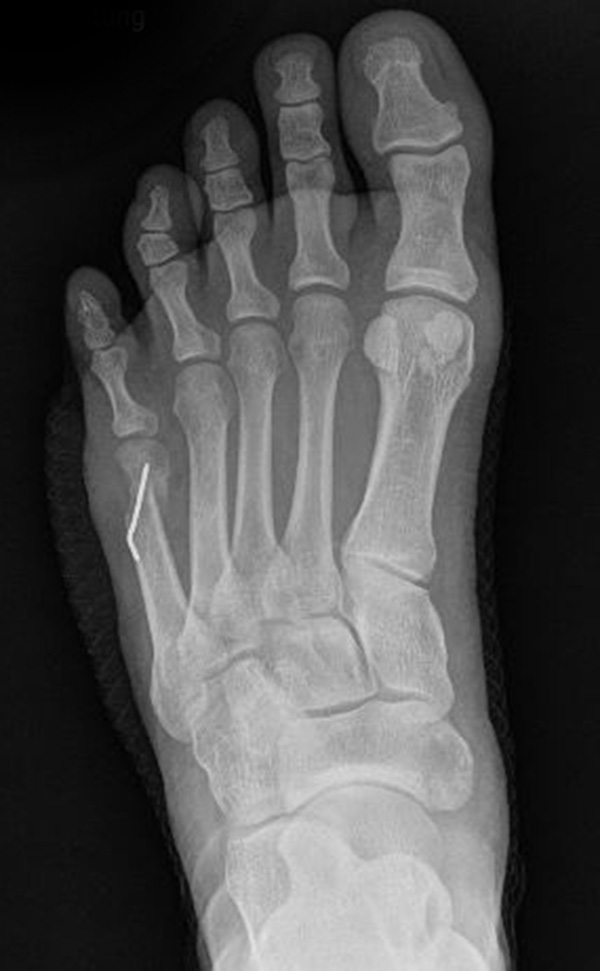

Abb. 7 a, b: Typ II Deformität mit prä- (a) und postoperativem Röntgenbild (b) mit K-Draht Osteosynthese und gleichzeitiger Hallux valgus Korrektur.

Abb. 8 a, b, c: Typ III Deformität mit prä- (a) und postoperativem Röntgenbild (b, c) mit Schrauben-Osteosynthese.

Abb. 9 a, b: Typ III Deformität mit prä- (a) und postoperativem Röntgenbild (b).